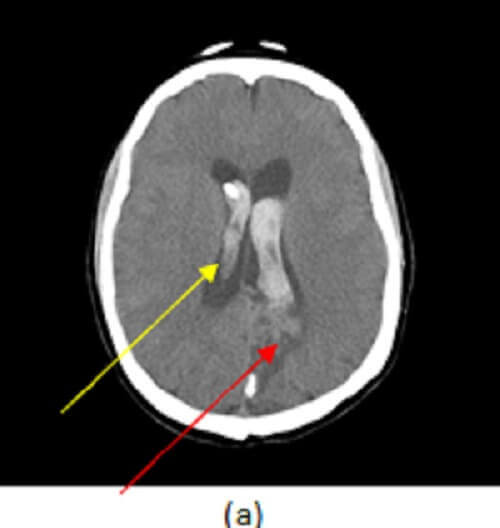

Figure 1: (a) axial image from a non contrast CT demonstrates intraparenchymal (yellow arrow) and intraventricular (red arrow) hemorrhage. (b, blue arrow), axial post contrast maximal intensity projection image from a CTA demonstrates a tangled vascular mass in the left parietal lobe consistent with an arteriovenous malformation (AVM). A saccular outpouching consistent with an intranidal aneurysm is also present adjacent to the ventricle (orange arrow). (c) Shaded surface display images show the AVM (green arrow) with early draining veins in to the deep (purple arrow) and superficial (white arrow) venous system. The intranidal aneurysm is also identified (brown arrow).